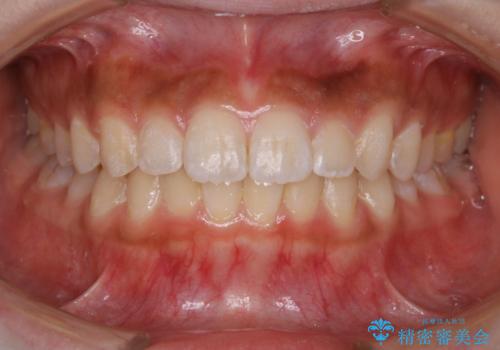

短期間ですきっ歯を改善:インビザラインLite

- 上の歯がすきっ歯なのと、歯が出ている気がするとご相談にいらした方です。

奥歯の噛み合わせに大きな問題がなく、患者様のご希望もあったため、前歯部メインで治療するインビザラインLiteで治療を行いました。

横顔のシルエットが改善し、口元もスッキリとなりました。